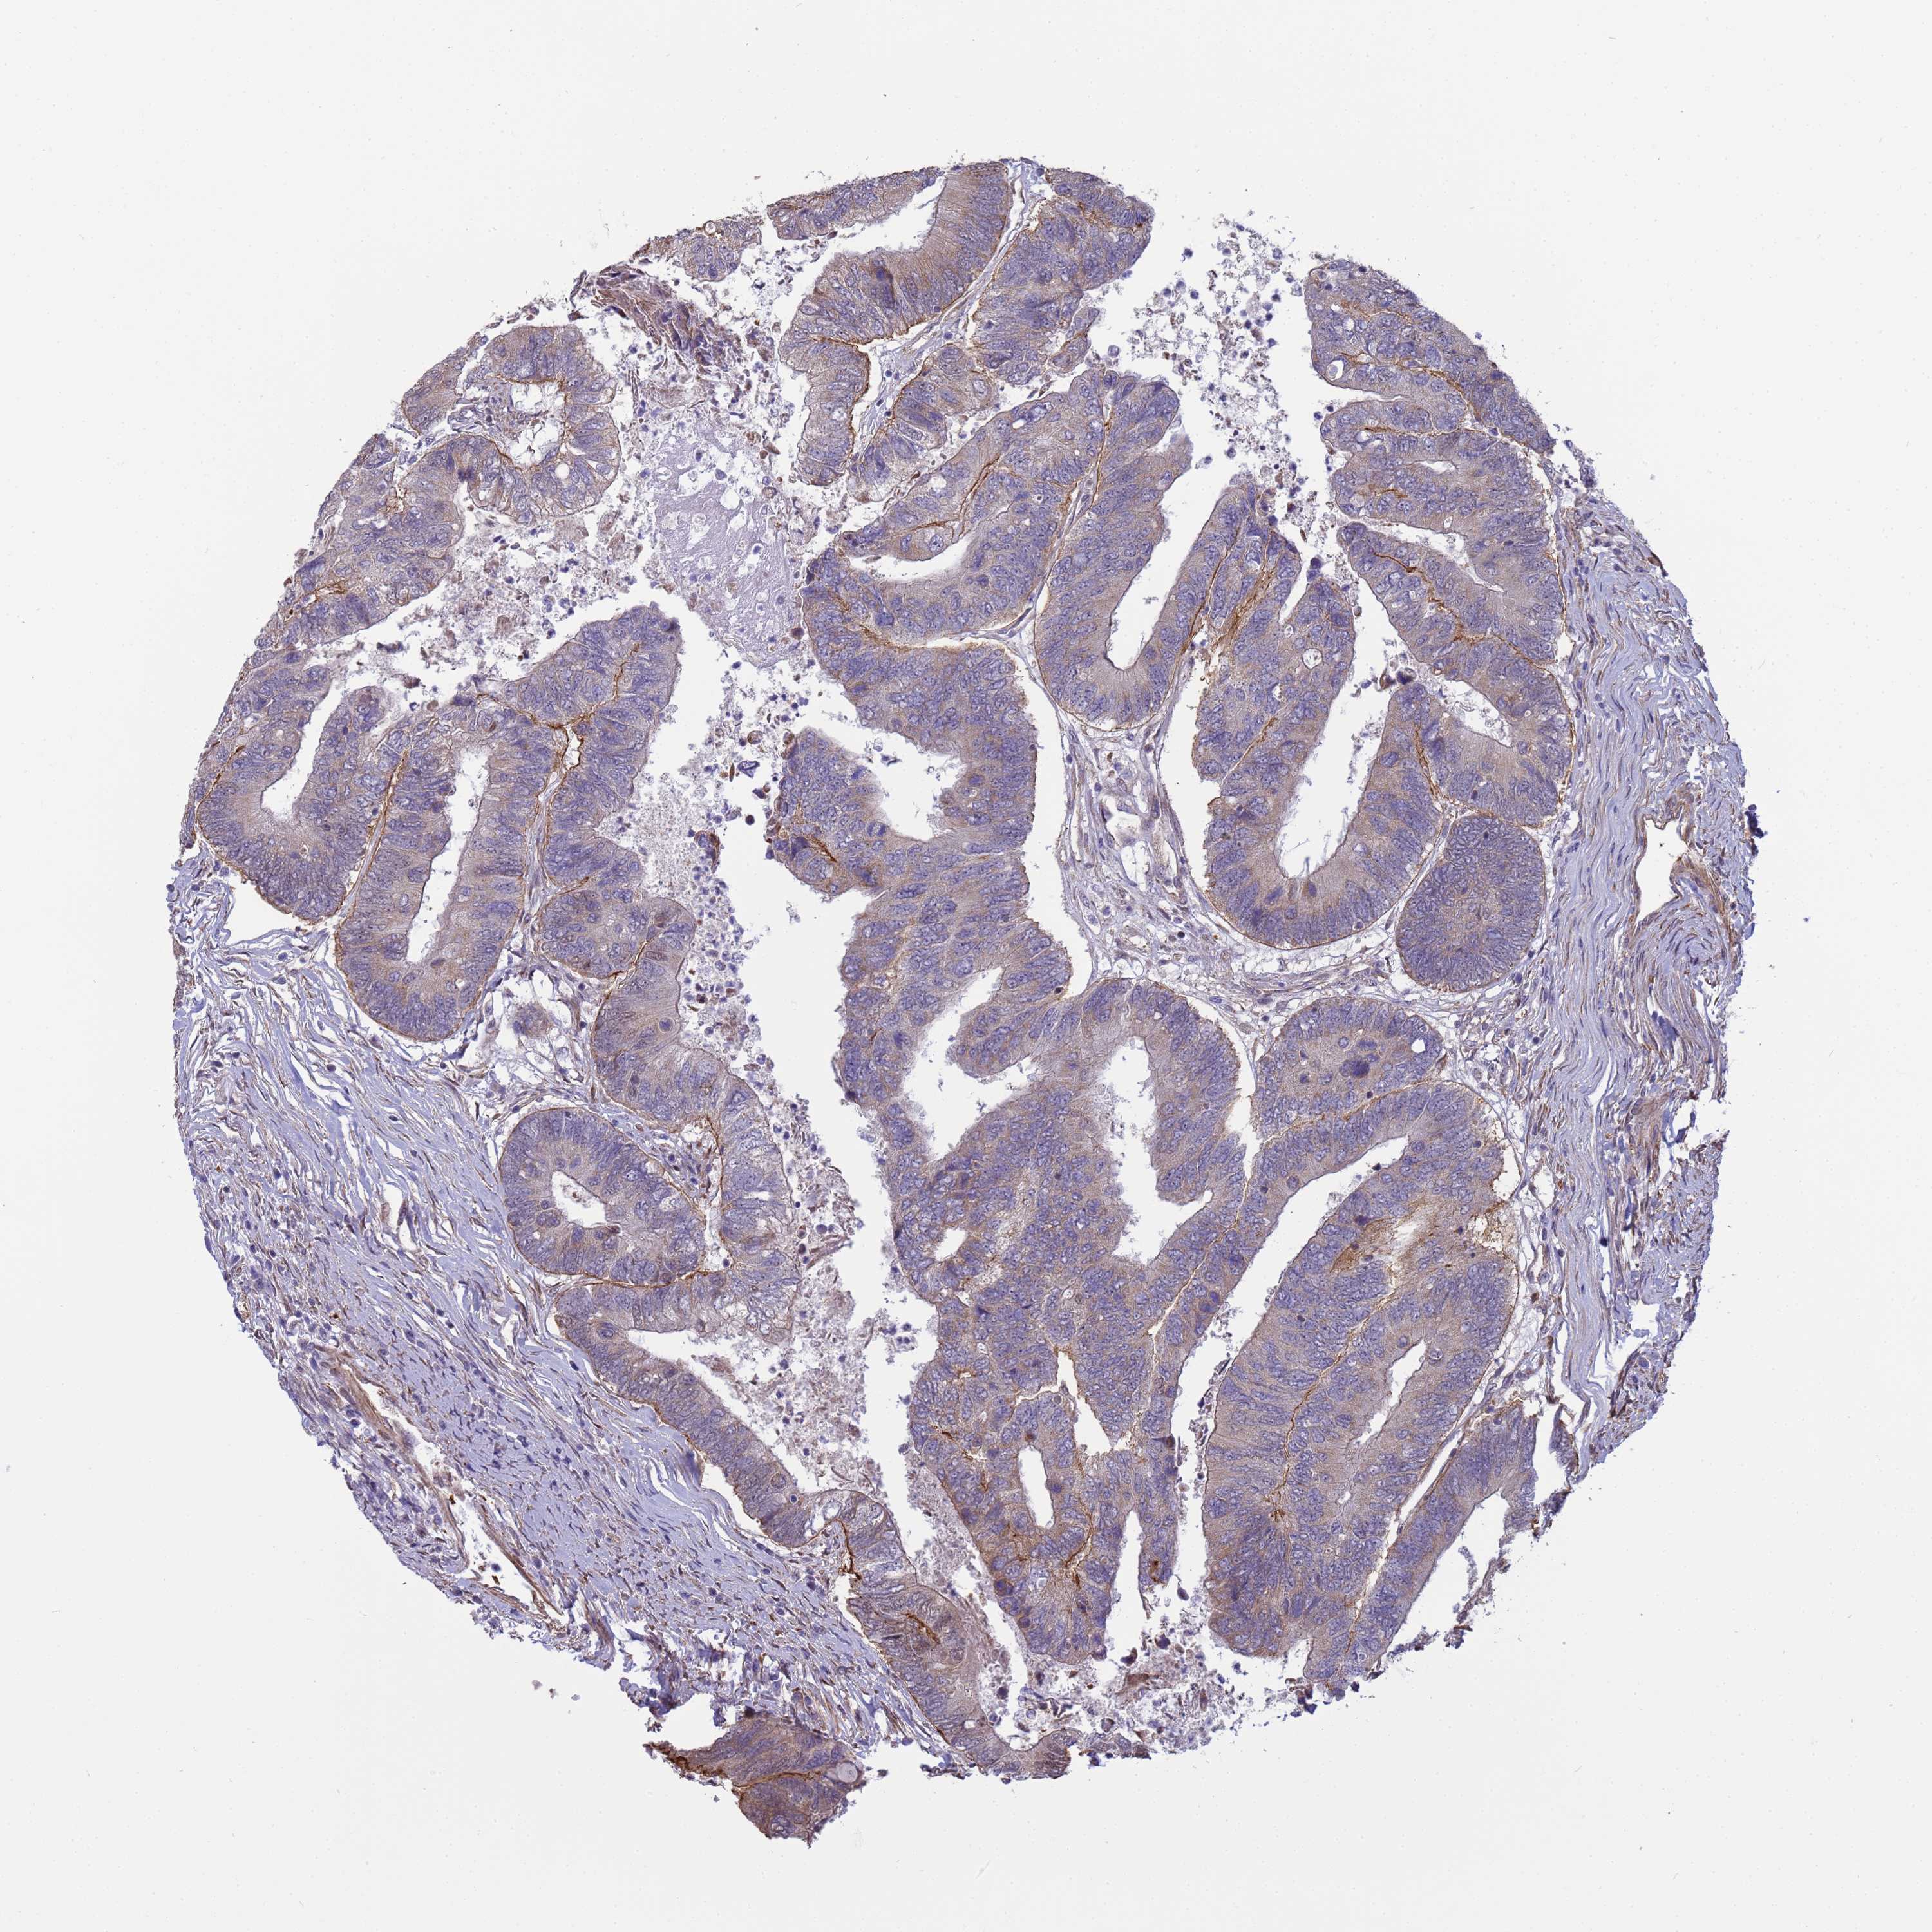

CANCER COLORECTAL CANCER Show tissue menu

Colorectal cancer

Human cancer

Colon adenocarcinoma